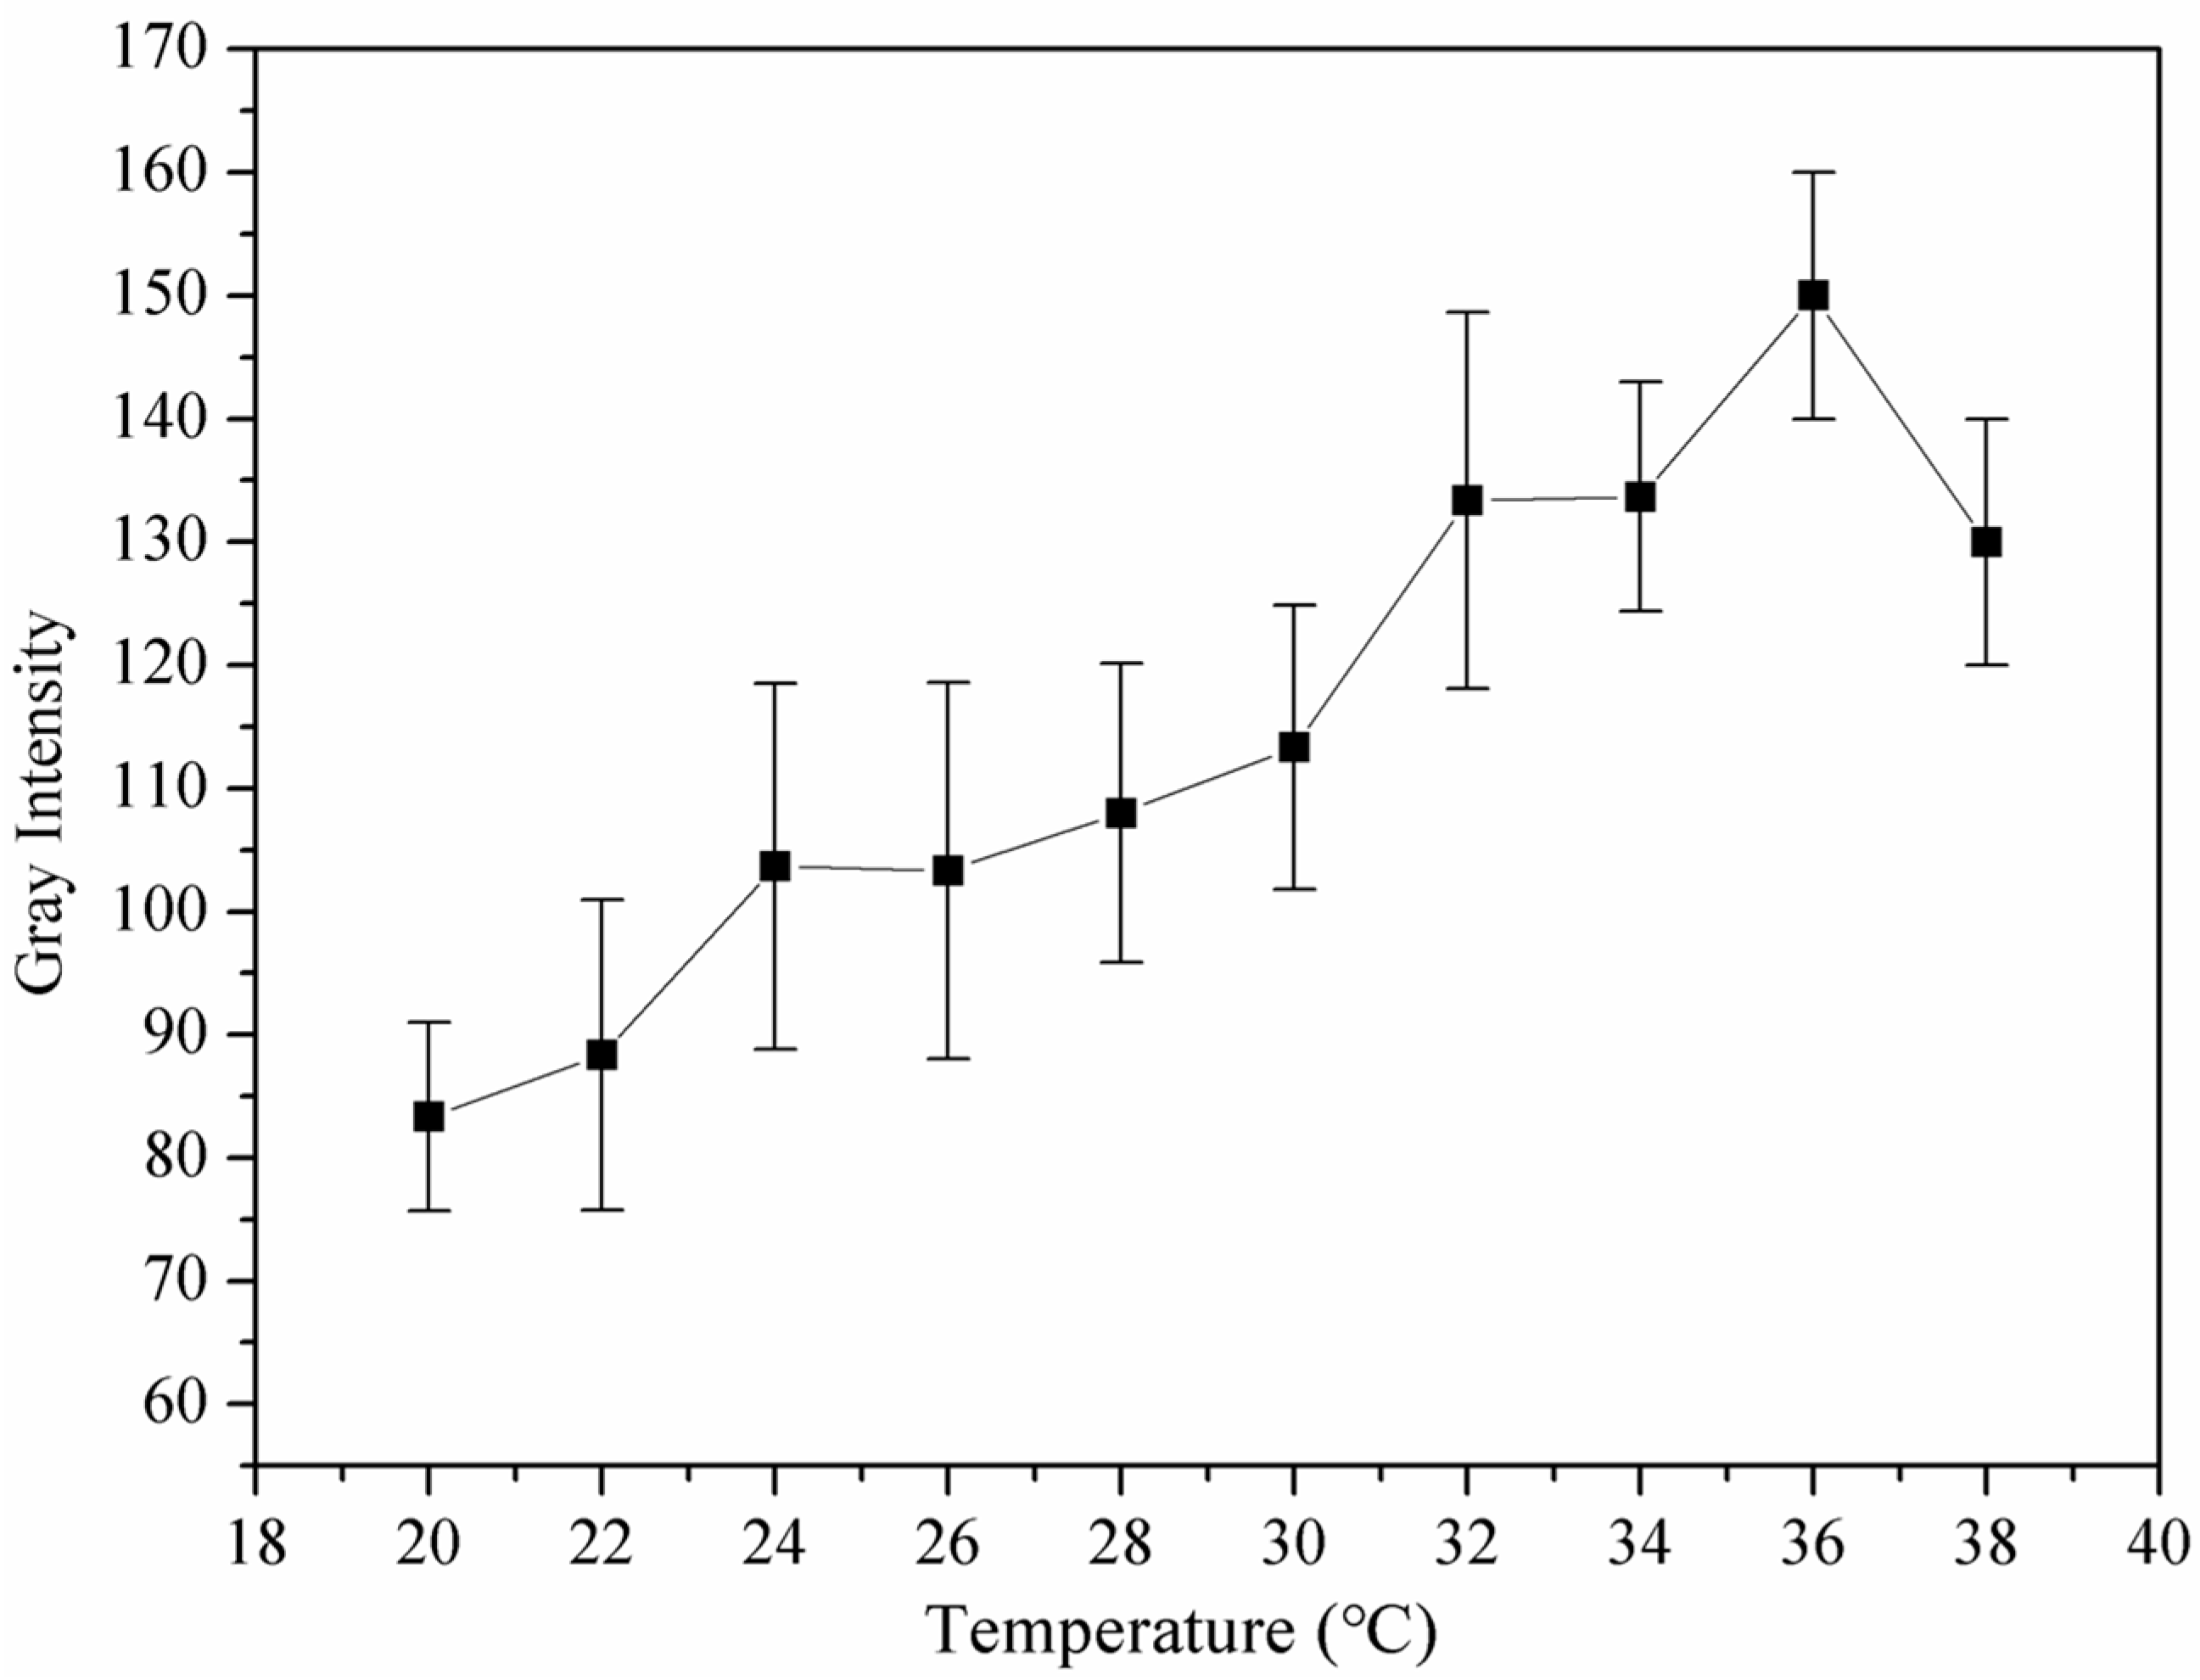

3.6. Ultrasound and Heat-Triggered Vaporization of Perfluoropentane